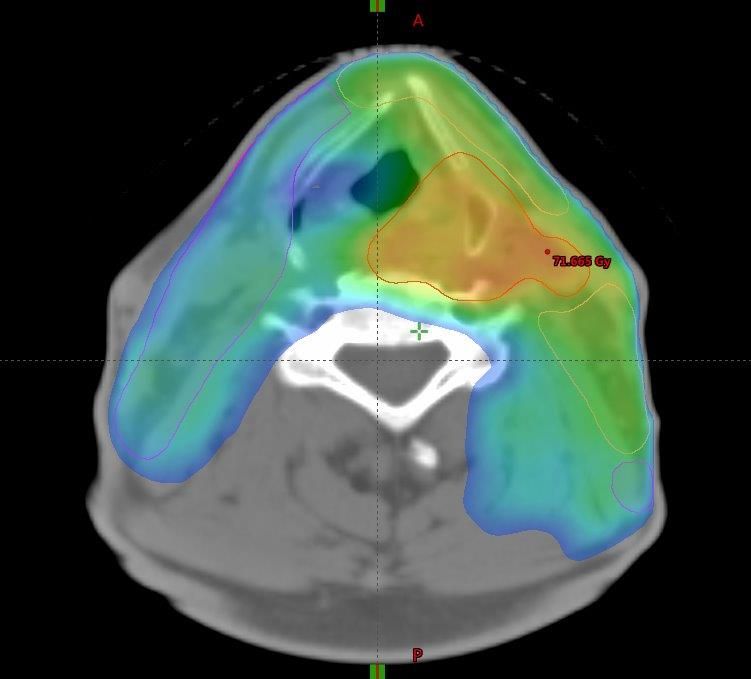

Tumore der Kopf-Hals-Region

Behandlungsplan Kopf-Hals-Region mit unterschiedlichen Dosisstufen (durch unterschiedliche Farben dargestellt).

Die Behandlung von Tumoren der Kopf-Hals-Region erfolgt in der Regel als intensitätsmodulierte Radiotherapie (IMRT) oder als intensitätsmodulierte Bogentherapie (Rapid Arc®) in parallel verabreichten unterschiedlichen Dosisstufen (sogenannter simultan integrierter Boost / SIB)